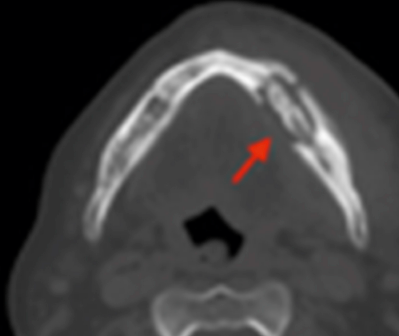

25

What are characteristic radiographic features of osteosarcoma?

* Sunray appearance * May see on OPG or CT * Expansion of periosteum

26

What is happening in this radiograph?

Osteosarcoma OR may be old fractured md that did not receive tx * Loss of continuity of LHS md * Irregular replacement of proximal and distal ends * Lysis extending into bony stumps